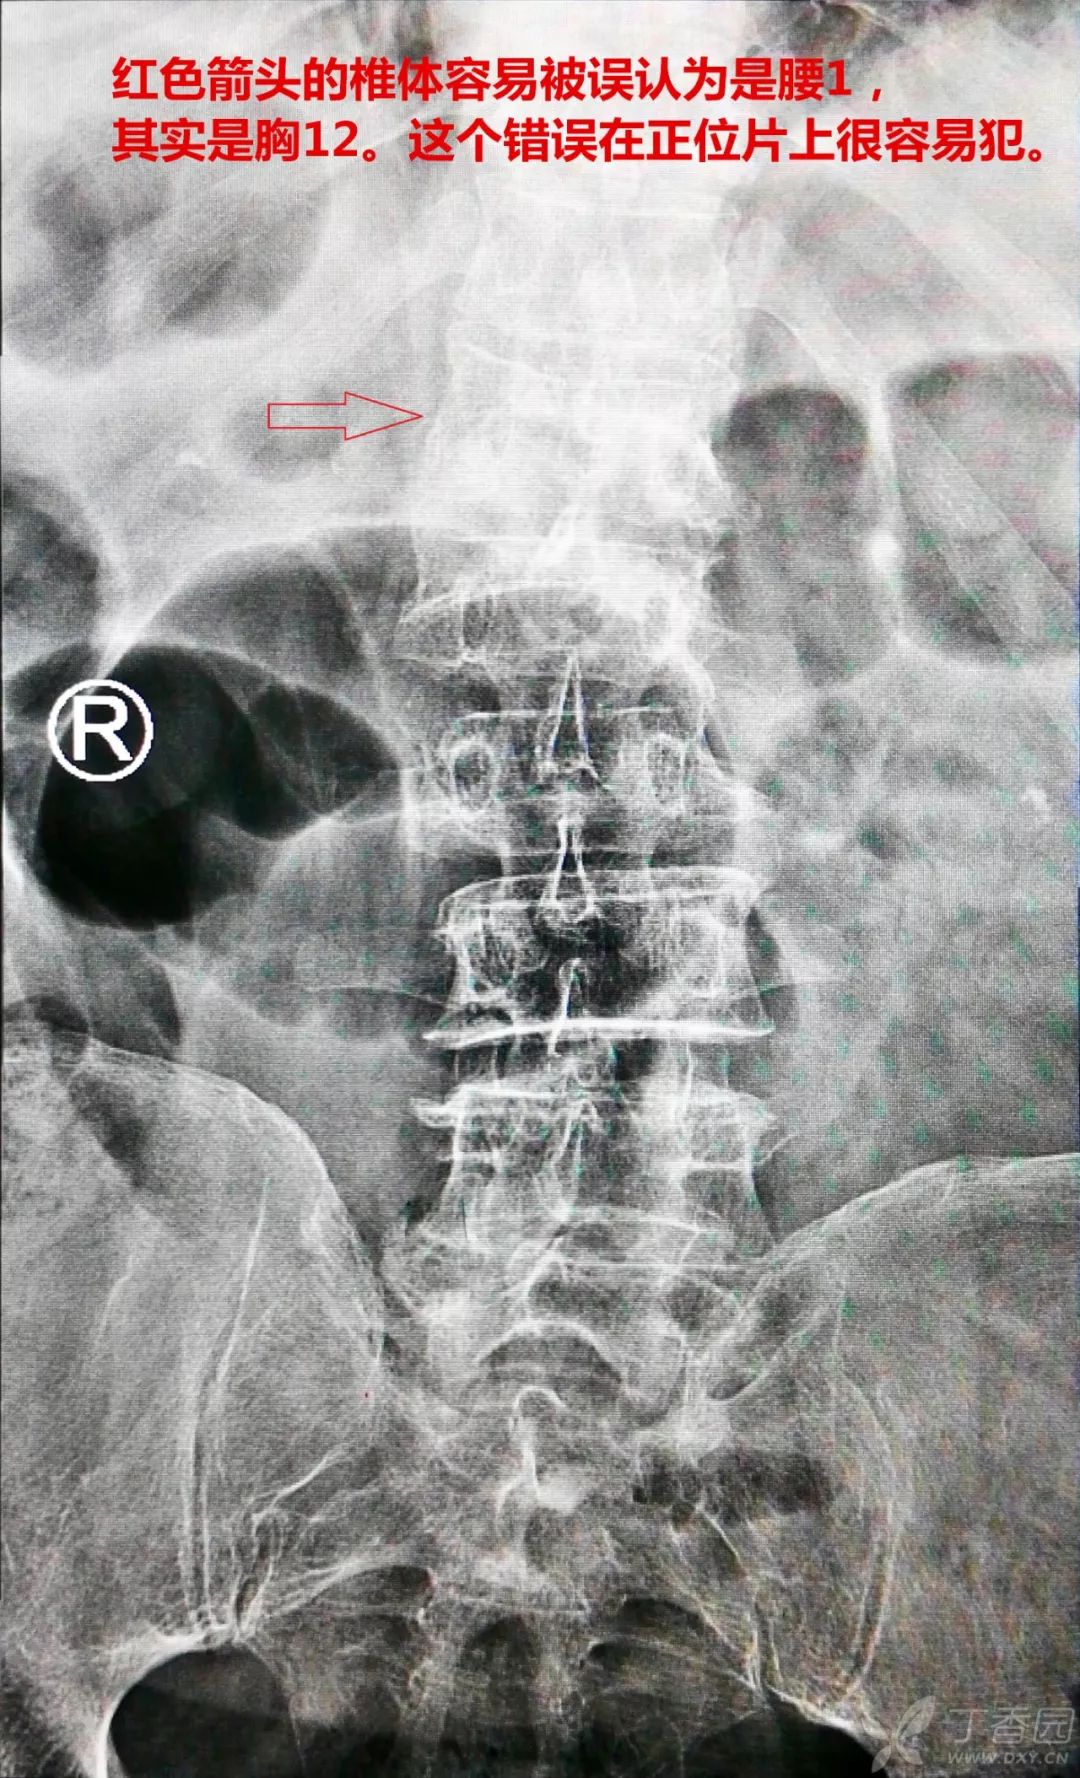

这个病例从正位片看,就很容易把胸 12 椎当做腰 1 椎体。尤其是胸 12 椎是陈旧骨折,椎体的形态也有压缩的时候,更容易混淆。

新鲜骨折的椎体在核磁上是非常明确的,「投射」到 X 线片上,就容易出现误判,因为我们习惯从肋骨和髂脊形态了判定椎体是哪一节,比如胸椎是有肋骨的,髂脊的高点是对着腰 4-5 的,但这些都不一定准确。

笔者从核磁和 X 线的侧位片来数责任椎或责任间隙,这两者是肯定对应的。在 X 线侧位片上定好责任椎或责任间隙后,再通过髂脊的位置来判断正位片的责任椎或责任间隙。

以这个病例为例,核磁上看到的责任椎在侧位 X 线上对应的,很容易找到(红色箭头),再看侧位片髂脊高点的位置(紫色箭头)。然后再到正位 X 线片上从髂脊高点位置开始数,这样就可以完全排除各种变异带来的干扰。

下面这张侧位 X 线片看,责任椎是髂脊高点上第三个椎体。那么回到正位片,我们同样也从正位片的髂脊高点往上数三个椎体,就一定是责任椎体。